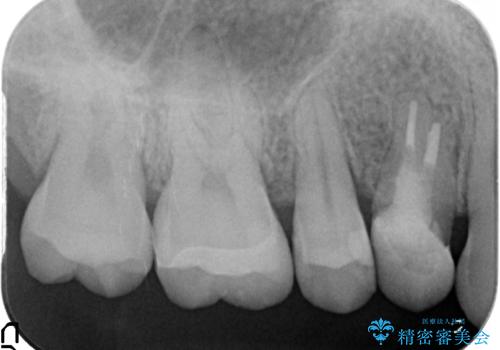

- 右上の奥歯で冷たいのもがしみるといらっしゃった方の症例です。

虫歯を除去後、セラミックインレーによる修復を行いました。